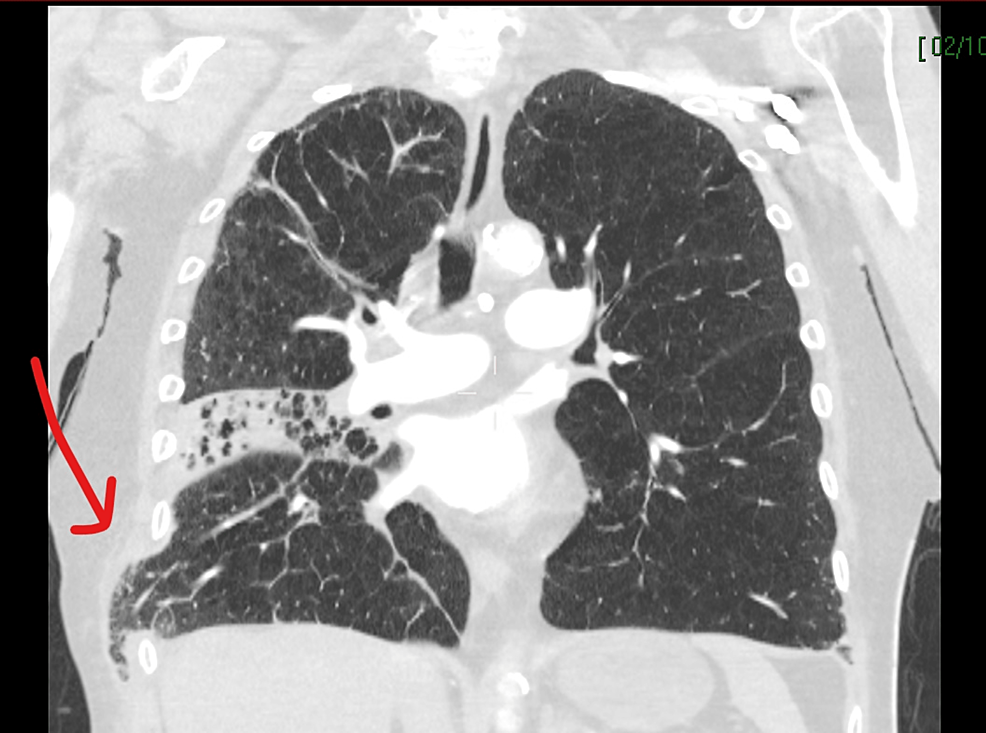

Fiberglass In Lung Lymph node biopsy showed granulomatous lymphadenitis with giant cell formation. in conclusion, our results show, for the first time in humans, that. we performed a systematic review of epidemiological evidence regarding respiratory cancer risks in relation to man. we performed a systematic review of epidemiological evidence regarding respiratory cancer risks in relation to man. while fiberglass may not stay in your lungs forever, it’s crucial to consider the potential health effects associated with. exposure to fiber glass has been shown to induce pleural and lung disorders such as emphysema, fibrosis. the best judgement was that in 36 (13.0%), pulmonary opacities or pleural. The mediastinal lymphadenopathy and the. fiberglass inhalation seems to produce a minimal tissue response in the lungs, and the reaction is one of macrophagic. Lymph node biopsy showed granulomatous lymphadenitis with giant cell formation. Computed tomography of the chest showed mediastinal lymph node enlargement and pulmonary infiltrates.